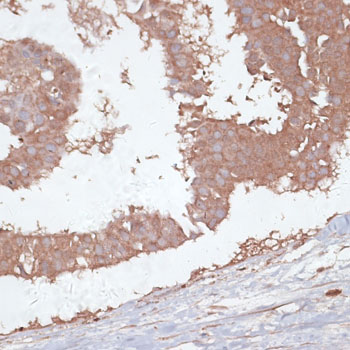

IHC (Immunohiostchemistry)

(Immunohistochemistry of paraffin-embedded human mammary cancer using TGFBR2 at dilution of 1:100 (40x lens).)